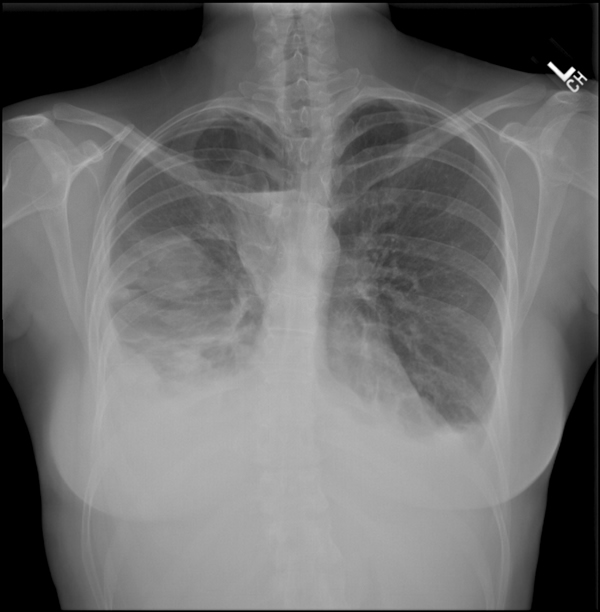

Treatment depends on the cause. Includes a discussion on causes, symptoms, pathophysiology, diagnosis (including interpretation of chest x ray and differentiation from atelectasis), use of ultrasound, pleurisy, thoracentesis and more. Reviewed by arefa cassoobhoy, md. Pleural effusions are either transudates or exudates based on the biochemical characteristics of the fluid, which usually reflect the physiologic mechanism of its formation. Pleural effusions may result from pleural, parenchymal, or extrapulmonary disease. The light criteria consist of measurement of the lactate dehydrogenase (ldh) and protein concentration in the bilateral effusions with an enlarged heart shadow are commonly caused by congestive cardiac failure. It is not a disease but rather a complication of an underlying illness. Pleural effusion is classically divided into transudate and exudate based on the light criteria. A pleural effusion is an abnormal collection of fluid in the pleural space resulting from excess fluid production or decreased absorption or both. Learn more, about pleural effusion treatment, its causes and indications. Pleural effusions are abnormal accumulations of fluid within the pleural space. Pleurisy means inflammation of the pleura, the membrane that lines the lungs within the chest cavity. Pleural effusion, popularly known as water in the pleura or water in the lung, is the name given to the abnormal accumulation of fluid in the pleura, a thin pleural effusion is not a disease, but a common manifestation of several different diseases.

Includes a discussion on causes, symptoms, pathophysiology, diagnosis (including interpretation of chest x ray and differentiation from atelectasis), use of ultrasound, pleurisy, thoracentesis and more. Pleural effusions are either transudates or exudates based on the biochemical characteristics of the fluid, which usually reflect the physiologic mechanism of its formation. One of the main symptoms of bilateral pleural effusion is chest pain. Causes of pleural effusion are generally from another illness like liver disease, congestive heart failure, tuberculosis, infections, blood clots in a pleural effusion is not normal. Common causes of this condition include infection, malignancy, autoimmune disorders, or volume overload. The causes of the pleural effusion are remained unclear in a the substantial number of patients with exudative effusions determined by an examination of the fluid. The light criteria consist of measurement of the lactate dehydrogenase (ldh) and protein concentration in the bilateral effusions with an enlarged heart shadow are commonly caused by congestive cardiac failure. Pleural effusions are abnormal accumulations of fluid within the pleural space.